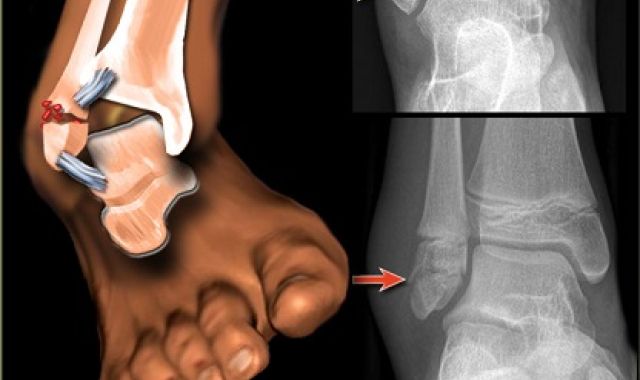

Chronic Ankle Instability

Chronic ankle instability is a condition characterized by a recurring giving way of the outer...

Early Mobilisation reduces the risk of complications in Ankle Fracture Fixation Surgery

Ankle fractures can occur during sporting activities, or as a result of a fall. Fractures can...